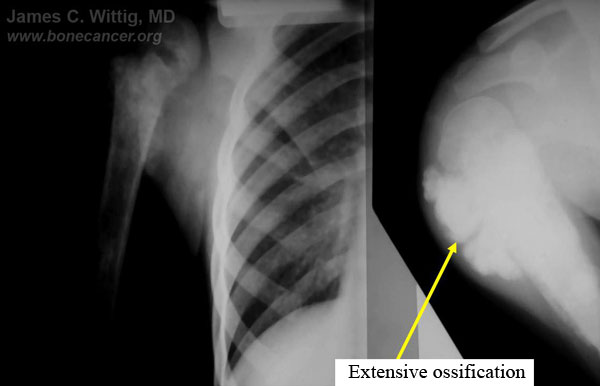

Gross Pathology: Osteosarcoma of Proximal Humerus

- originates from metaphysis of the proximal humerus, extends into surrounding soft tissues

- large soft tissue component that is crossing the glenohumeral joint

- was removed via an extra-articular resection, including scapula (Tikhoff-Linberg resection)